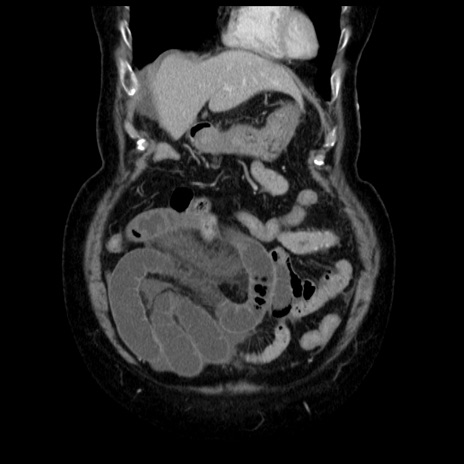

症例13(冠状断像)

【症例】70歳代女性

【主訴】腹痛、嘔吐

【現病歴】15時間程前(昨晩)より腹痛あり。今朝になっても症状の改善なく、嘔吐あり。腹痛も増悪あり、救急外来受診。

【既往歴】子宮癌全摘術後

【身体所見】意識清明、BP 121/72mmHg、P 74bpm、SpO2 100%(RA)、腹部:平坦・軟、腸雑音ほぼ聴取せず。下腹部・心窩部・臍左上に圧痛あり。反跳痛なし。

【データ】WBC 10600、CRP 0.15